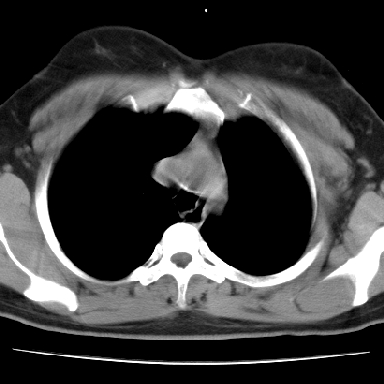

左下肺肿块影,内可以见小泡征,并见厚壁空洞形成,洞内缘凹凸不平,可见壁结节。靠近胸膜侧可见胸膜凹陷征。左侧胸腔内可见少量低密度积液影。双肺可见多发性小结节影。

考虑:左下肺癌性空洞伴两肺转移

左下肺肿块影,内可以见小泡征,并见厚壁空洞形成,洞内缘可见壁结节。靠近胸膜侧可见胸膜肥厚粘连。双肺可见多发性小结节影。

考虑:左下空洞性肺癌伴两肺转移